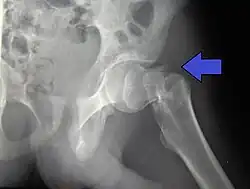

Fracture (black arrow, pertrochanteric) versus a skin fold (white arrow).

X-rays of the affected hip usually make the diagnosis obvious; AP (anteroposterior) and lateral views should be obtained.